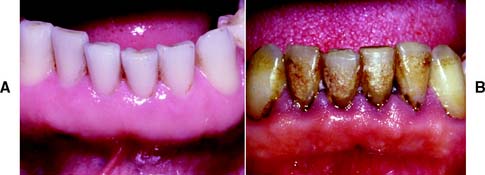

Healthy gingiva (Fig. 1-15A) is pink, stippled, and firmly bound to the underlying connective tissue. The free margin of the gingiva is knife-edged, and sharply pointed papillae fill the interproximal spaces. Any deviation from these findings should be noted. With the development of chronic marginal gingivitis (Fig. 1-15B), the gingiva becomes enlarged and bulbous, loss of stippling occurs, the margins and papillae are blunted, and bleeding and exudate are observed.

Fig. 1-15 A, Healthy gingiva: pink, knife-edged, and firmly attached. B, Gingivitis: Plaque and calculus have caused marginal inflammation, with changes in color, contour, and consistency of the free gingival margin. Inflammation extends into the keratinized attached gingiva.